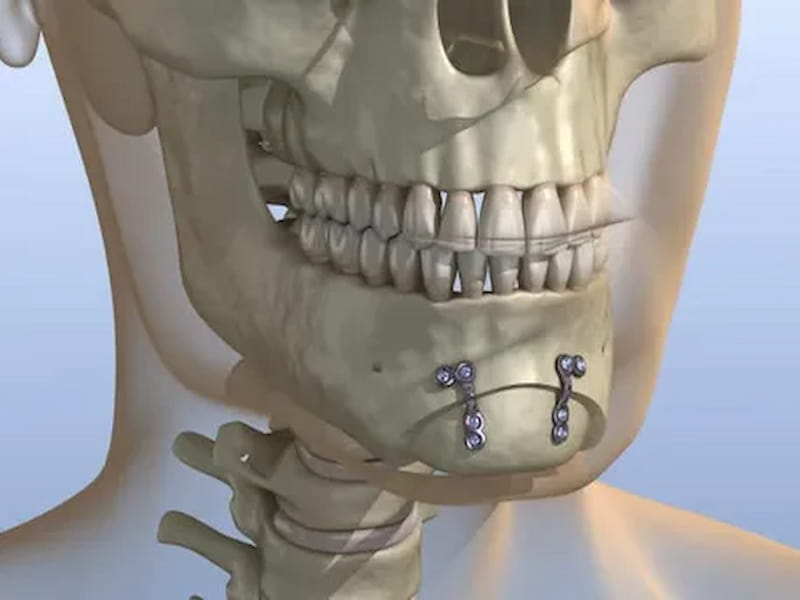

ایمپلنت فک پایین

ظاهراً ایمپلنت دندان یک مفهومی بسیار پیچیده و گیج کننده است، اما در واقع، این روش جبران دندان ها با استفاده از جراحی و ایجاد تعامل مستقیم با استخوان فک برای ارائه پایه قوی برای دندان های مصنوعی است.

در طول زمان، نوع های مختلفی از ایمپلنت های دندان برای جبران دندان های عقب فک پایین توسط تولیدکنندگان و شرکت های مختلفی معرفی شده اند.

مشخصات ایمپلنت فک پایین

برخی از انواع ایمپلنت دندان در بازار شامل ایمپلنت های فلزی، ایمپلنت های سرامیکی و ایمپلنت های ترکیبی می باشند.

ایمپلنت های فلزی از جمله تیتانیوم و آلومینیوم است که بسیار قوی و با دوام هستند.

به علاوه، ایمپلنت های سرامیکی به عنوان جایگزینی برای ایمپلنت های فلزی پیشنهاد می شوند، زیرا ظاهر طبیعی تری دارند و قادر به تقلید دقیق از رنگ دندان های طبیعی هستند.